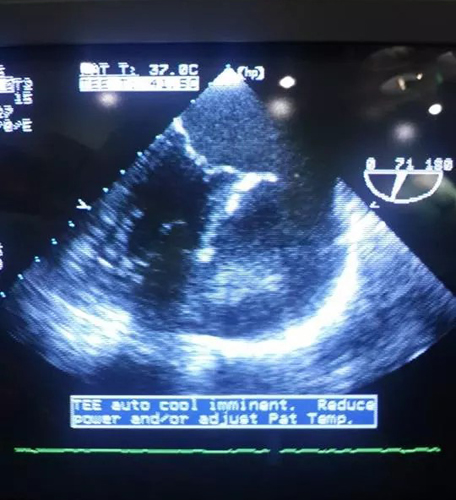

Ուլտրաձայնային սրտագրություն. խոռոչային գոյացություն՝ 7x8 սմ չափսերով, ինչը հաղորդակցվում է ձախ նախասրտի ականջիկի հետ և իր մեջ ներառում կլորավուն, մեծ խտությամբ զանգված՝ 5x6 սմ չափսերով: Նշված զանգվածը ճնշում է գործադրում ձախ նախասրտի պատին և ձախ փորոքի կողային պատին:

Համակարգչային տոմոգրաֆիա. խոռոչային գոյացություն՝ 7x8 սմ չափսերով, ինչը հաղորդակցվում է ձախ նախասրտի ականջիկի հետ և իր մեջ ներառում կլորավուն, մեծ խտությամբ զանգված՝ 5x6 սմ չափսերով: Նշված զանգվածը ճնշում է գործադրում ձախ նախասրտի պատին և ձախ փորոքի կողային պատին:

Ս/թ փետրվարի 19-ին սրտային վիրաբուժության բաժանմունքի վարիչ Վ. Գասպարյանը առաջատար մասնագետներ Ա. Հայրապետյանի, Ա. Սևոյանի և պրոֆեսոր Պ. Վոգտի (Շվեյցարիա) ուղղակի մասնակցությամբ իրականացրել է վիրահատություն. հեռացվել է նախասրտի ականջիկից դուրս եկող դիվերկուլ հիշեցնող խոռոչային հսկայական օվալաձև գոյացություն՝ նման սպիտակ թրոմբի (5x6սմ): Արդյունքում, դիվերտիկուլի հեռացումից անմիջապես հետո, հենց վիրահատական սեղանին վերականգնվել է սինուսային ռիթմը: